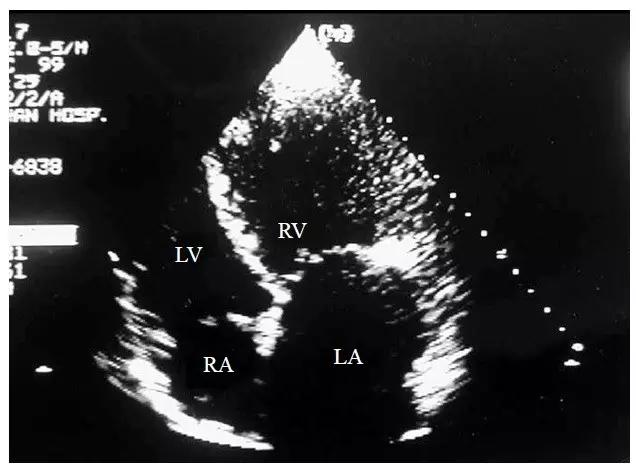

图10-4-7 大动脉转位心室左襻的二维超声心动图表现

心尖四腔心切面示右心室位于左侧,左心室位于右侧,三尖瓣隔叶的位置较二尖瓣低,右心室内可见调节束(LA-左心房 LV-左心室 RA-右心房 RV-右心室)